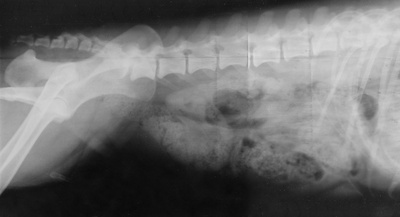

Röntgen am Rücken hat meist keinen Sinn

Bild: Dirk Kruse / pixelio.de